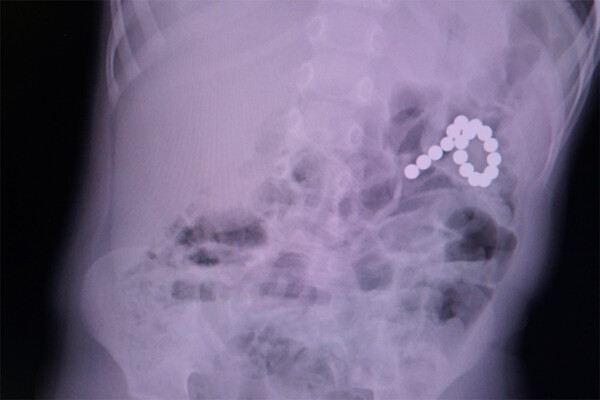

Хирурги ЯНАО прооперировали мальчика с 17 магнитами в желудке и кишечнике

На Ямале врачи извлекли из двухлетнего ребенка 17 магнитных шариков

Врачи Ямала прооперировали ребенка, который проглотил 17 магнитных шариков. Об этом сообщает Департамент здравоохранения ЯНАО.

Изначально медики подозревали у двухлетнего мальчика коронавирус, но во время обследований в Ноябрьской городской больнице у него нашли детали от магнитного конструктора. Часть элементов осталась в желудке, остальные прошли в кишечник и проделали отверстия в органах.

Врачи оперативно прооперировали ребенка. Во время манипуляции из пациента извлекли шарики и зашили отверстия. На данный момент мальчик чувствует себя хорошо.

По словам хирурга, проводившего операцию, подобные конструкторы опасны для маленьких детей. Даже два магнита могут существенно навредить ребенку.